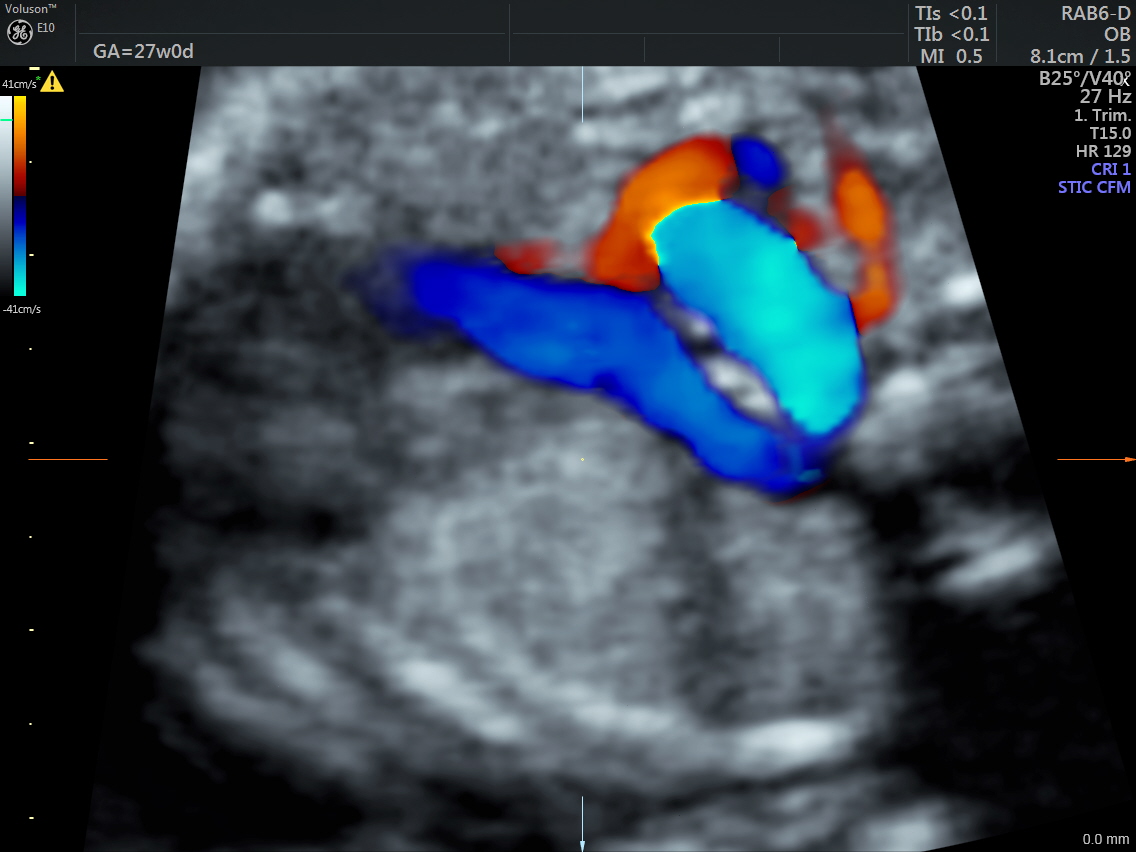

Power Doppler shows a turbulent junction of the aortic and ductal arches suggestive of Kommerel’s diverticulum.

The aberrant left subclavian artery arising from the Kommerel’s diverticulum is seen in the next two pictures.